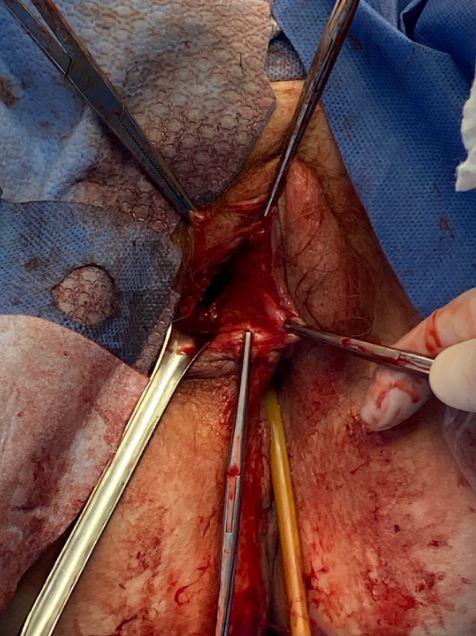

MRI of the pelvis was obtained and showed interval resolution of right vulvar abscess and persistent sinus tract extending from the skin at the level of the prior vulvar abscess extending into the pubic symphysis (Figure 3). Orthopedic surgery and infectious disease specialties were once again consulted for further recommendations and management. Per infectious disease recommendations, repeat blood and wound cultures were obtained. She then underwent additional surgical management by gynecology and orthopedics. Gynecology debrided the right vulvar skin, subcutaneous tissue and wound to the level of the pubic symphysis (Figure 4). Additionally, through an abdominal approach, orthopedic team p obtained access via a Pfannenstiel incision to evaluate the pubic symphysis and surrounding bone (Figure 5). The infected bone and surrounding tissue structures were thoroughly debrided and copiously irrigated, and wound was packed with 1g of vancomycin powder. Wound cultures obtained intra-operatively showed anti-microbial resistance to vancomycin, therefore per infectious disease recommendations, she was transitioned to daptomycin 10mg/kg every 24hrs and ceftaroline 600mg IV every 8 hrs. Ongoing wound care was provided with daily wet to dry dressing changes. Patient was discharged home in stable condition on post-operative day 6 and had daily home health visits for administration of IV antibiotics and wound care. She continued to be seen weekly in the ambulatory gynecology clinic. Her vulvar wound as well as abdominal incision showed progressively marked improvement and healing.

Figure 4 Gynecology debrided the right vulvar skin, subcutaneous tissue and wound to the level of the pubic symphysis.